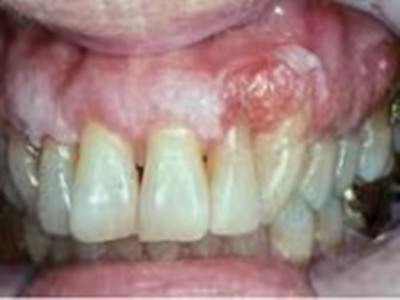

牙龈癌多源于牙间乳头及龈缘区,溃疡呈表浅、淡红,以后可出现增生。由于黏骨膜与牙槽突附着甚紧,较易早期侵犯牙槽突骨膜及骨质,进而出现牙松动,并可发生脱落。X线片可出现恶性肿瘤的破坏特征虫蚀状不规则吸收。

牙龈癌常发生继发感染,肿瘤伴以坏死组织,触之易出血。体积过大时可出现面部肿胀,浸润皮肤。